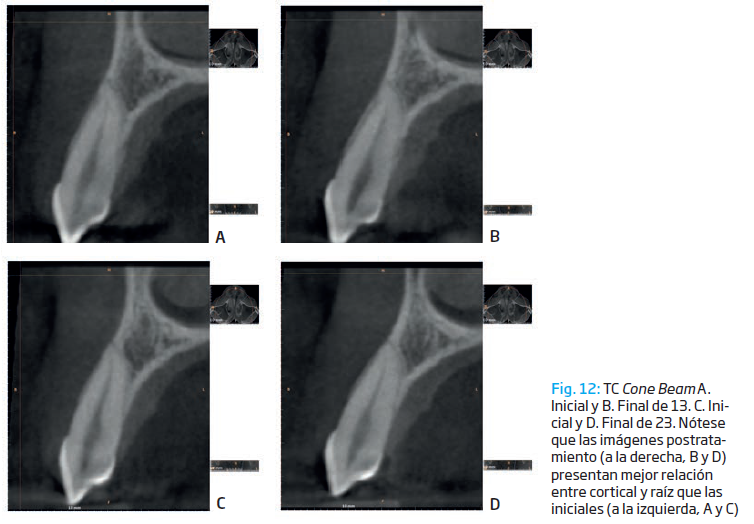

En la tomografía inicial se observan fenestraciones que desaparecieron en dos de tres piezas al finalizar el tratamiento, como es el caso de las piezas 13 y 23. La mayoría de las piezas dentarias no mostraron cambios en la altura de la cresta ósea vestibular; en tres piezas, aumentó y en dos de ellas, disminuyó. (Fig. 12)